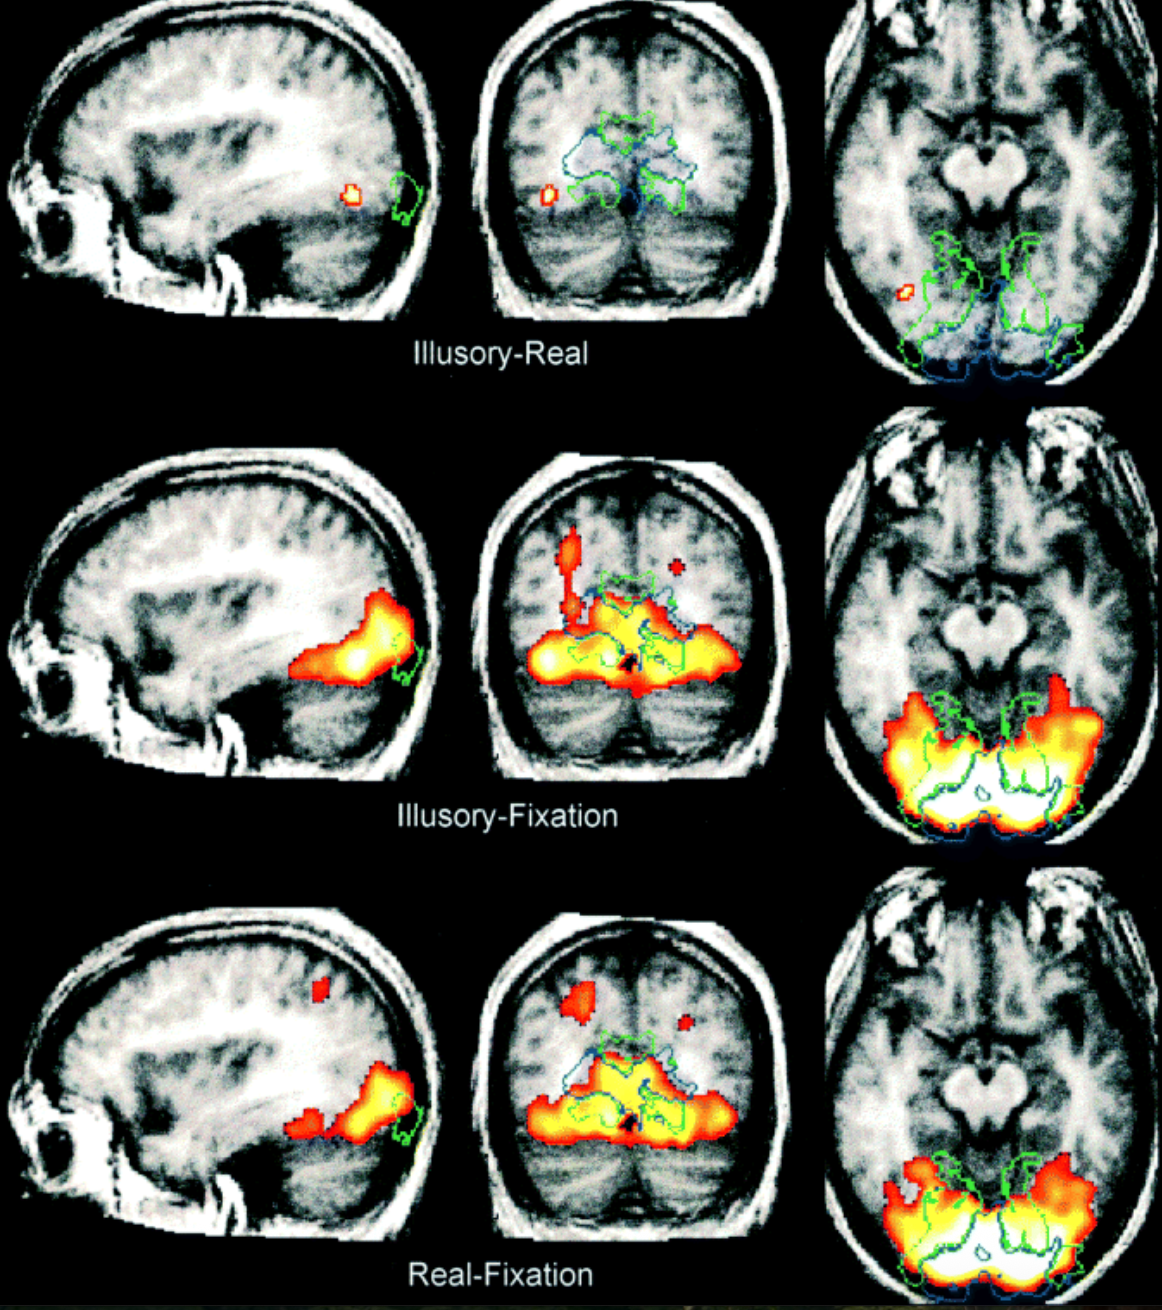

Exploratory: Neural correlates of illusory shapes

Hypothesis-driven: Are illusory shapes represented in the dorsal visual stream?